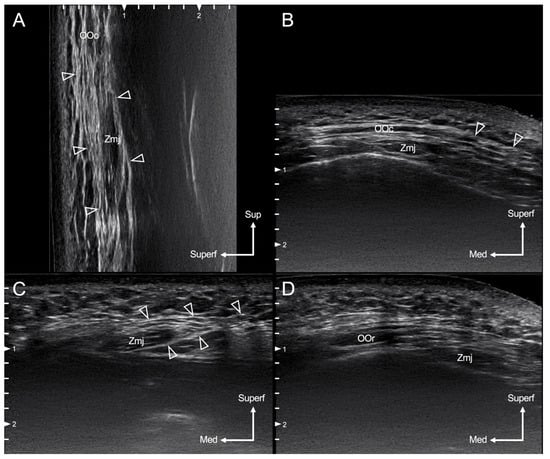

3.3. Ultrasound Images of the Layered Relationship of the SMAS with Zmj and OOc